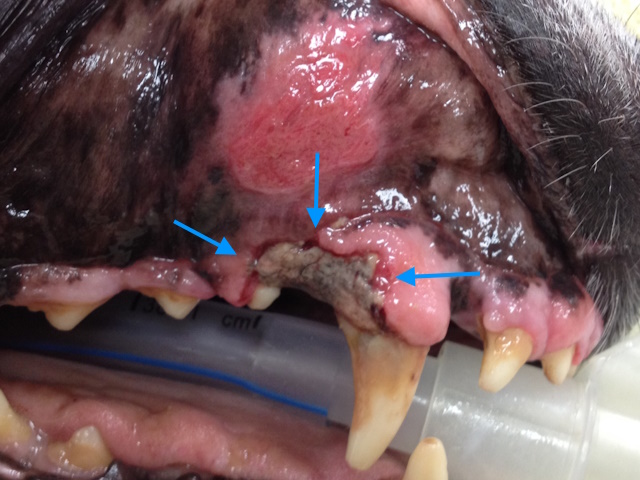

A cyst was identified next to the maxillary fourth premolar tooth (yellow arrows) consistent with a furcation cyst.

On dental radiograph it was hard to see the cyst, since it was not too big. But a periapical lesion is seen around the palatal root of first molar tooth.